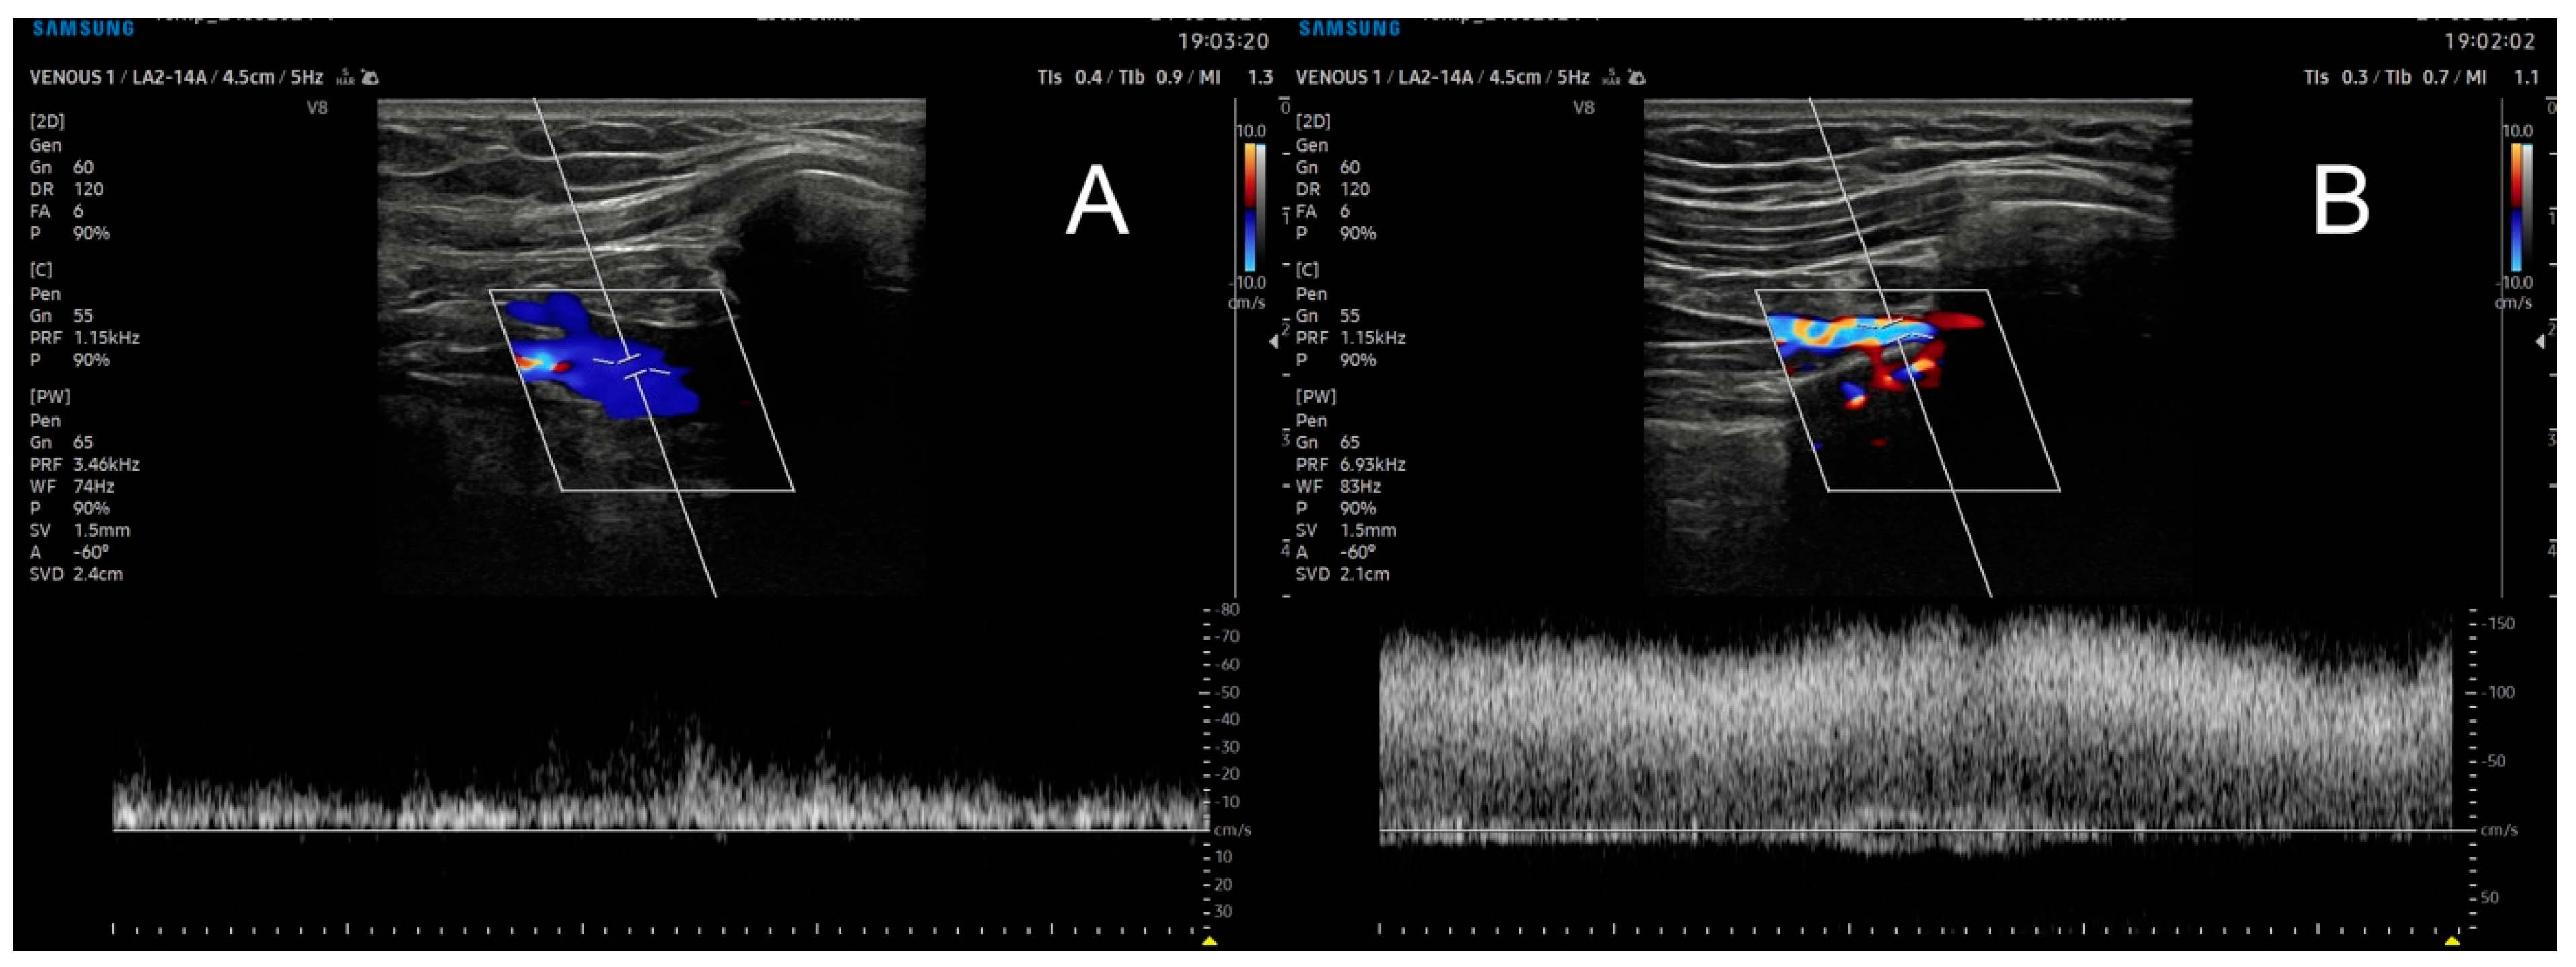

Imaging examination can take two forms. The first is the more available functional ultrasound examination, which, depending on the degree of compression by bone structures, may show narrowing and increased flow, or complete vessel occlusion depending on the degree of abduction/flexion of the upper limb in the shoulder joint (Figure 2).

Figure 2. Ultrasound examination of the subclavian vein in resting position (A) and in abduction to 90 degrees (B), with a high increase in flow near occlusion.